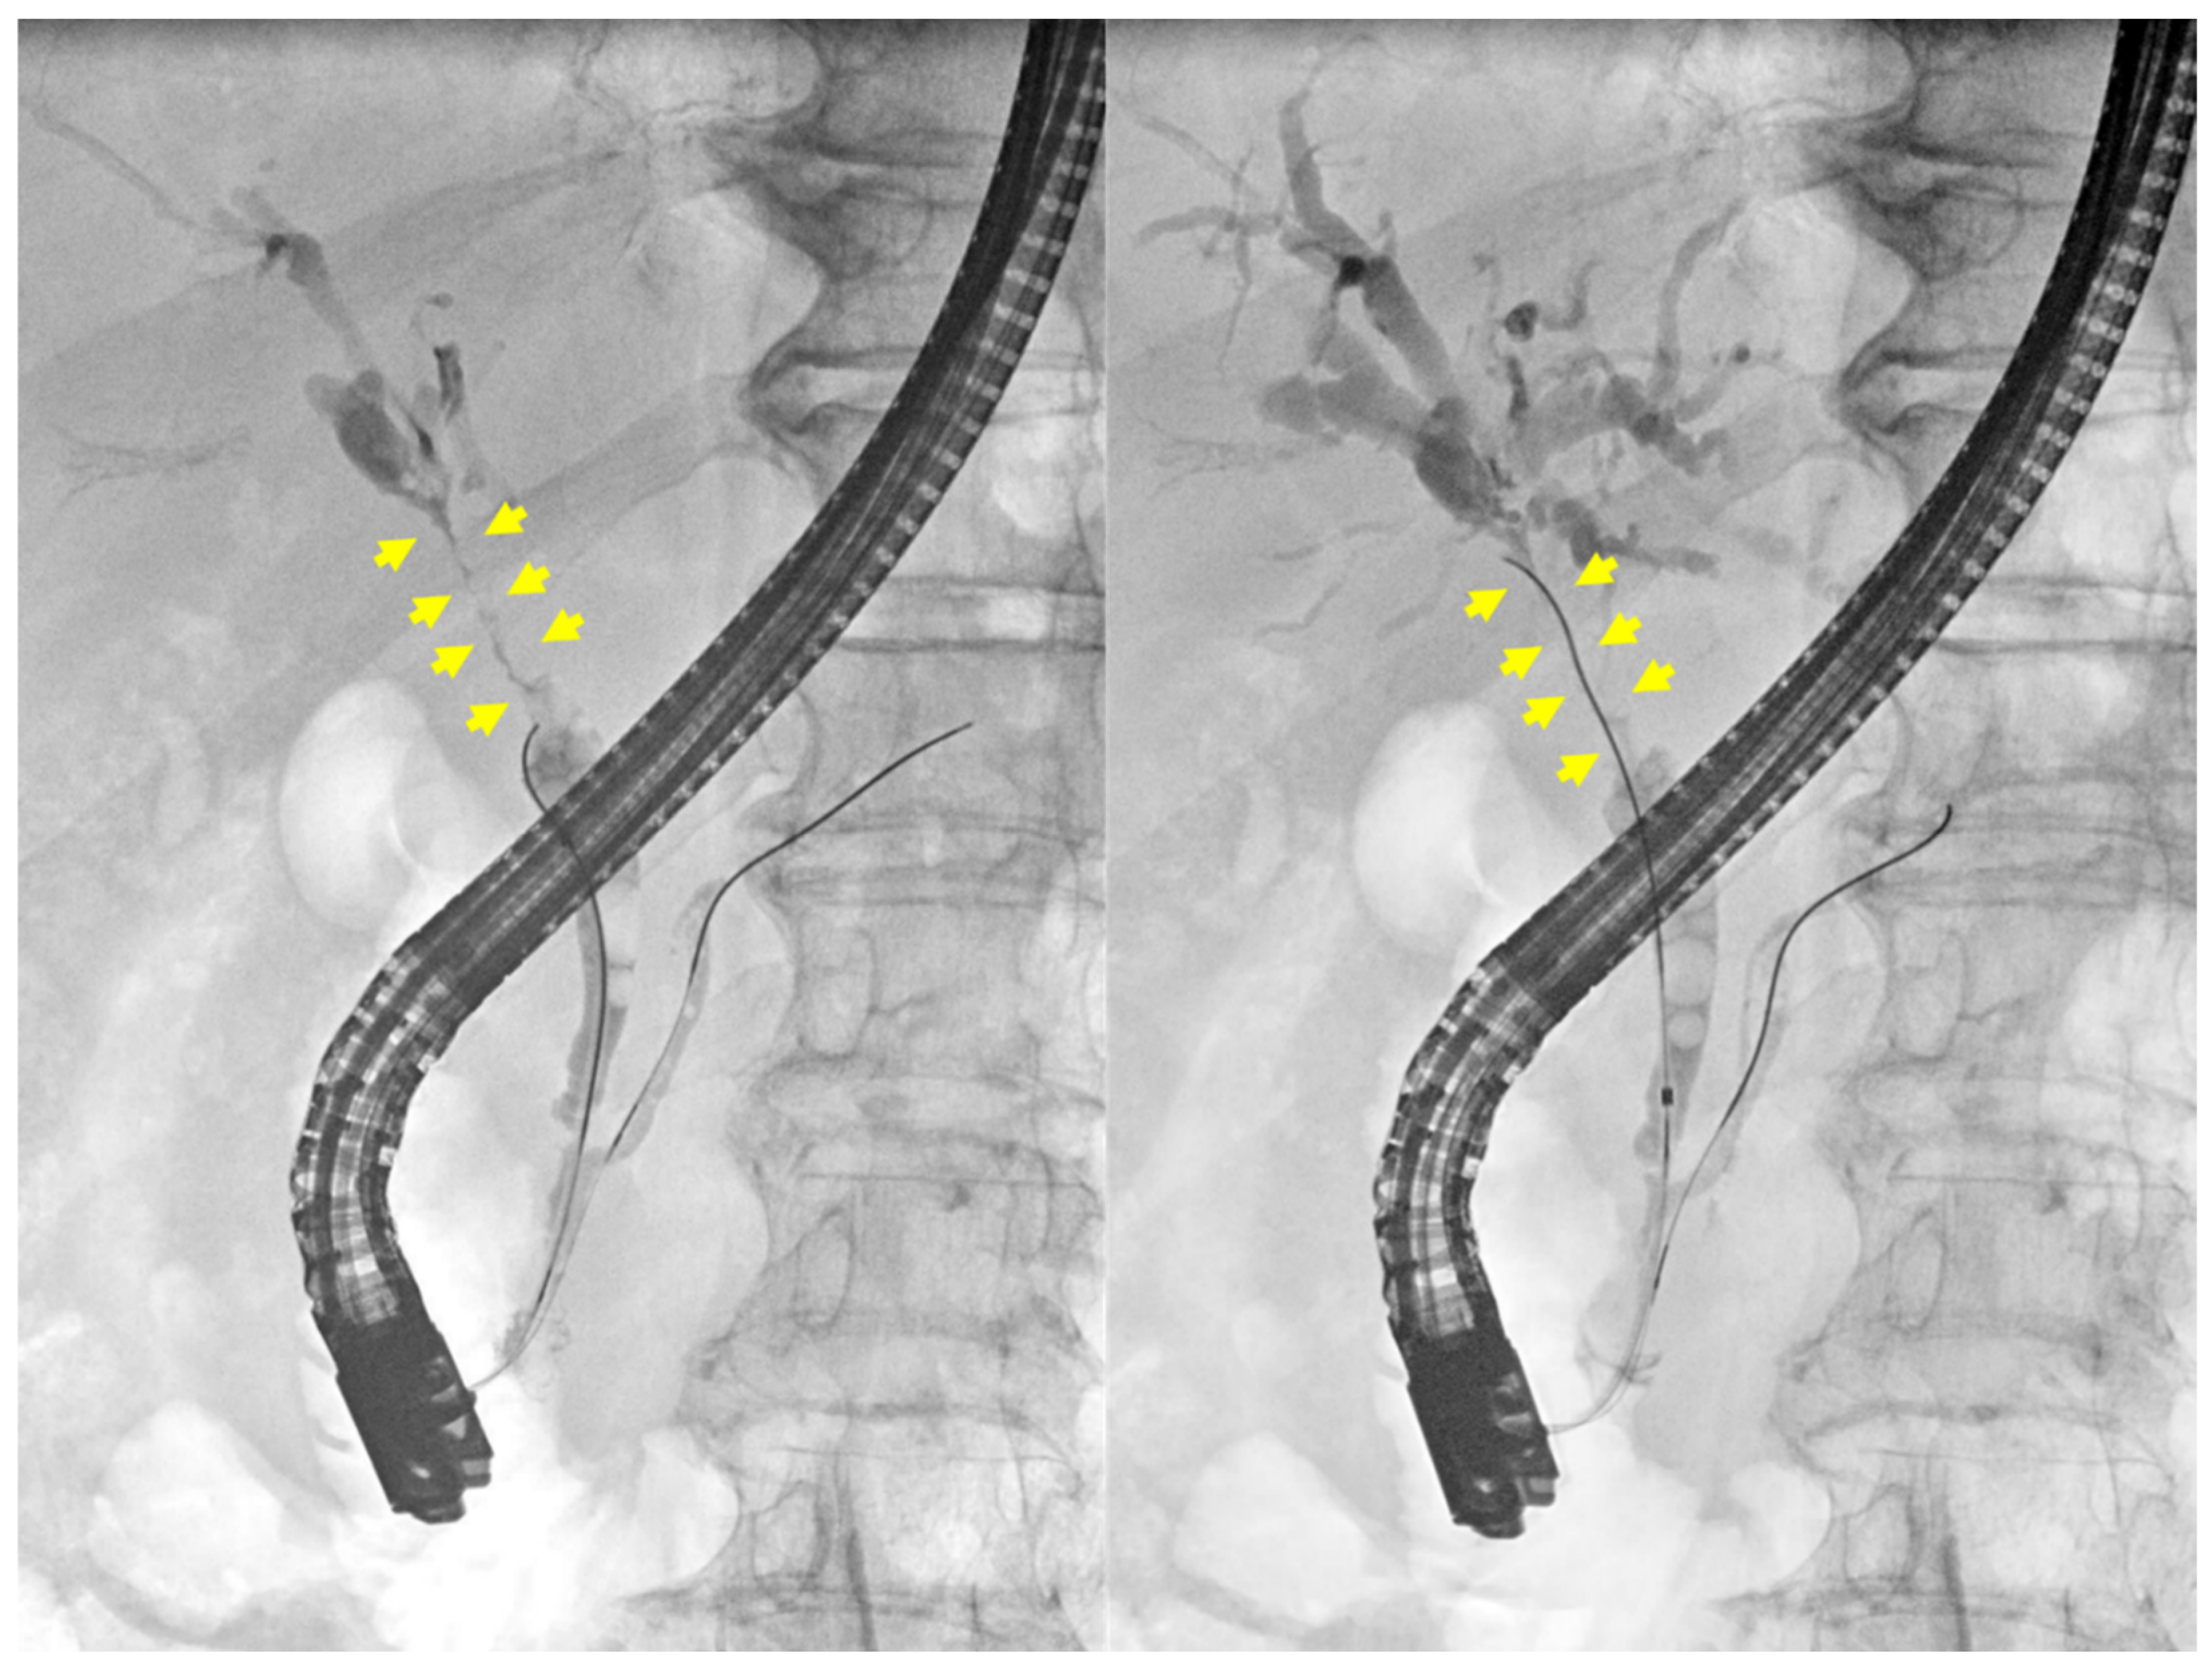

2. Case Presentation